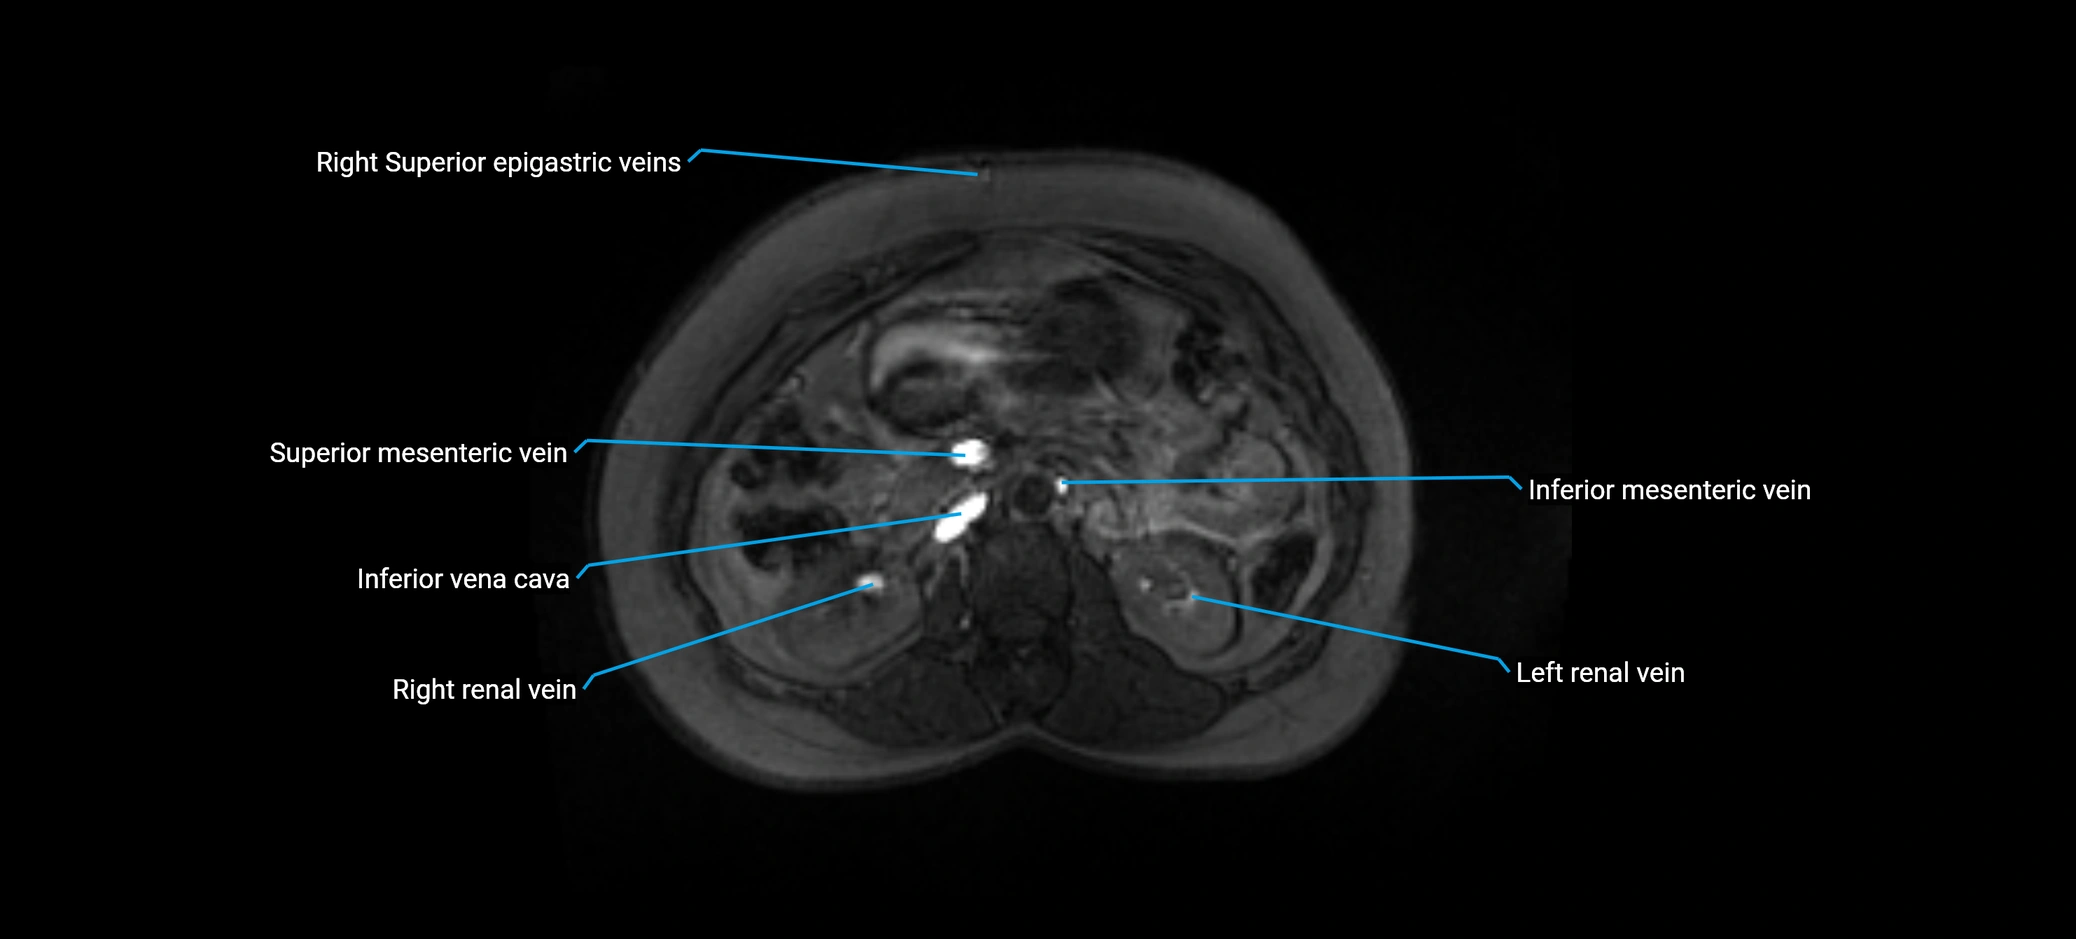

The anterior right branch of the portal vein is a major intrahepatic division of the right portal vein. After the main portal vein bifurcates into right and left branches, the right portal vein divides into anterior and posterior segmental branches.

The anterior right branch supplies the anterolateral liver segments (Segment V) and anteromedial liver segments (Segment VIII) within the right hepatic lobe. It operates as a key vascular route delivering nutrient-rich portal venous blood to the central and superior right liver.

MRV TOF (Time-of-Flight MR Venography):

• Appears as a bright, high-signal vascular channel representing flowing blood

• Clearly shows branching pattern of right portal vein into anterior and posterior branches

• Best in coronal or axial reconstructions for segmental mapping

• No need for contrast, relies on flow-related enhancement

MRI image

image